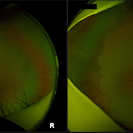

Bilateral Macular Colobomata With Temporal Dragging of Optic Disc

Apr 24 2020 by Dinesh Rungta, MBBS, DNB

Optos ultra-widefield retinal image of a 7-year-old male child showing bilateral macular colobomata with temporal dragging of optic disc.

Photographer: Dr Shivam Madan, Giridhar Eye Institute, Kerala, India

Imaging device: Optos UWF Daytona Plus

Condition/keywords: bilateral macular colobomata, temporal dragging of optic disc